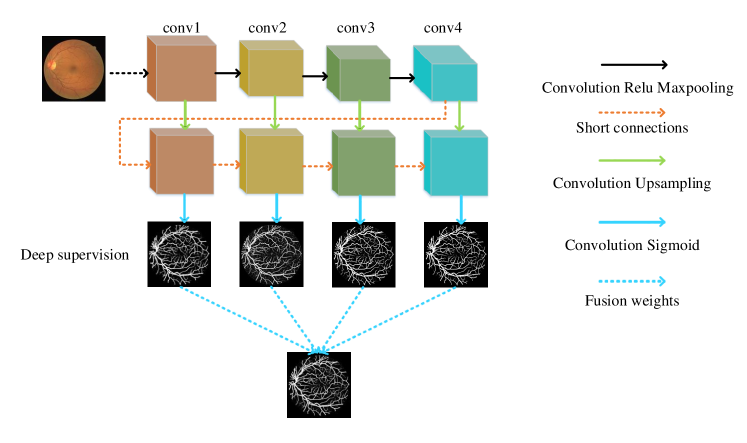

To overcome the aforementioned problem, we propose a deeply supervised neural network with short connections for vessel segmentation. The overview of the BTS-DSN is illustrated in Figure 2. Short connections are adopted to reduce noises of side-output1 as well as to make side-output4 less blurry. The following subsections will describe the BTS-DSN in details.

2.1 Deep supervision

As is well known, it is hard to optimize a deep neural network due to the gradient vanish problem [28]. To alleviate the gradient vanish problem and obtain a good vessel map, we use deep supervision information in the BTS-DSN. Figure 3 gives an illustration of HED, DSN, BS-DSN and BTS-DSN. We can observe that DSN is based on HED except that there are only four side-output layers, and extra hidden layers are added in DSN for better utilizing deep supervision information. When bottom-top short connections are added to DSN, we get BS-DSN. Further, when top-bottom short connection is added to BS-DSN, we get BTS-DSN.

2.2 Bottom-top short connections

We adopted bottom-top short connections to deliver detail information just as shown in Figure 4. There are three bottom-top short connections in total. Suppose we use VGGNet as backbone. We can observe from Figure 4 that there are four groups of convolution (conv1, conv2, conv3 and conv4) for feature learning in total. We first convolved the last convolution of each group using 16 convolution kernels with size 11. Then, the obtained feature maps are up-sampled 1, 2, 4, 8 respectively to restore to original resolution. Bottom-top short connections are among feat_conv1, feat_conv2, feat_conv3, and feat_conv4.

Let’s take bottom-top short connection between feat_conv1 and feat_conv2 as an example (see Figure 5). The information (feat_1_2) passed from feat_conv1 is concatenated with feat_conv2 to get feat_conv2_fuse. Then, one hand hand, we perform a 11 convolution operation on feat_conv2_fuse to get the information (feat_2_3) delivered to feat_conv3. On the other hand, we performed convolution operation with a kernel size of 11 and sigmoid transformation for feat_conv2_fuse sequentially to obtain the segmentation result (side 2). At last, side 2 is compared with the ground truth to get the loss of the second side-output layer.

2.3 Top-bottom short connection

Bottom-top short connections aim to refine high-level segmentation results. However, we can observe from the first two rows in Figure 1 that the vessel map generated by the first side-output layer contains too many noises while the map generated by the last side-output could capture the main vessel structure. Therefore, we propose delivering high-level structural information to the first side-output layer to reduce its noises. We implemented this kind of information delivery by a top-bottom short connection from conv4 to feat_conv1, which can been seen in Figure 4. We first convolved the last convolution of conv4 using 1 convolution kernels with size 33. Then the obtained feature map are up-sampled 8 to get feat_4_1. The information (feat_4_1) passed from conv4 are concatenated with feat_conv1 to form feat_conv1_fuse (see Figure 5). At last, one hand hand, we perform a 11 convolution operation on feat_conv1_fuse to get the information (feat_1_2) delivered to feat_conv2. On the other hand, we performed convolution operation with a kernel size of 11 and sigmoid transformation for feat_conv1_fuse sequentially to obtain the segmentation result (side 1). At last, side 1 is compared with the ground truth to get the loss of the first side-output layer.

2.4 Inference